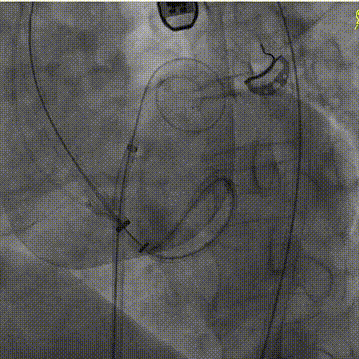

手术采用左侧股动脉入路与右侧股静脉入路,由股动脉入路将环形放置导管输送至瓣下预估深度并推送出合适角度,在高位开始多角度指引下导丝成环步骤。多学科团队紧密协作,在术前规划的DSA投射体位和科雨彤教授的超声引导配合下,宋光远教授精细操控,导丝顺利按预期路径环绕二尖瓣瓣叶,一次成型并将导丝头端送入升主,随后于升主中进行导丝抓捕,影像下对导丝环轨道进行充分验证,最后将导丝头端体外化,建立起固定环植入的重要轨道。

导丝围绕二尖瓣瓣叶成环

抓捕导丝并在超声下对导丝环位置进行验证